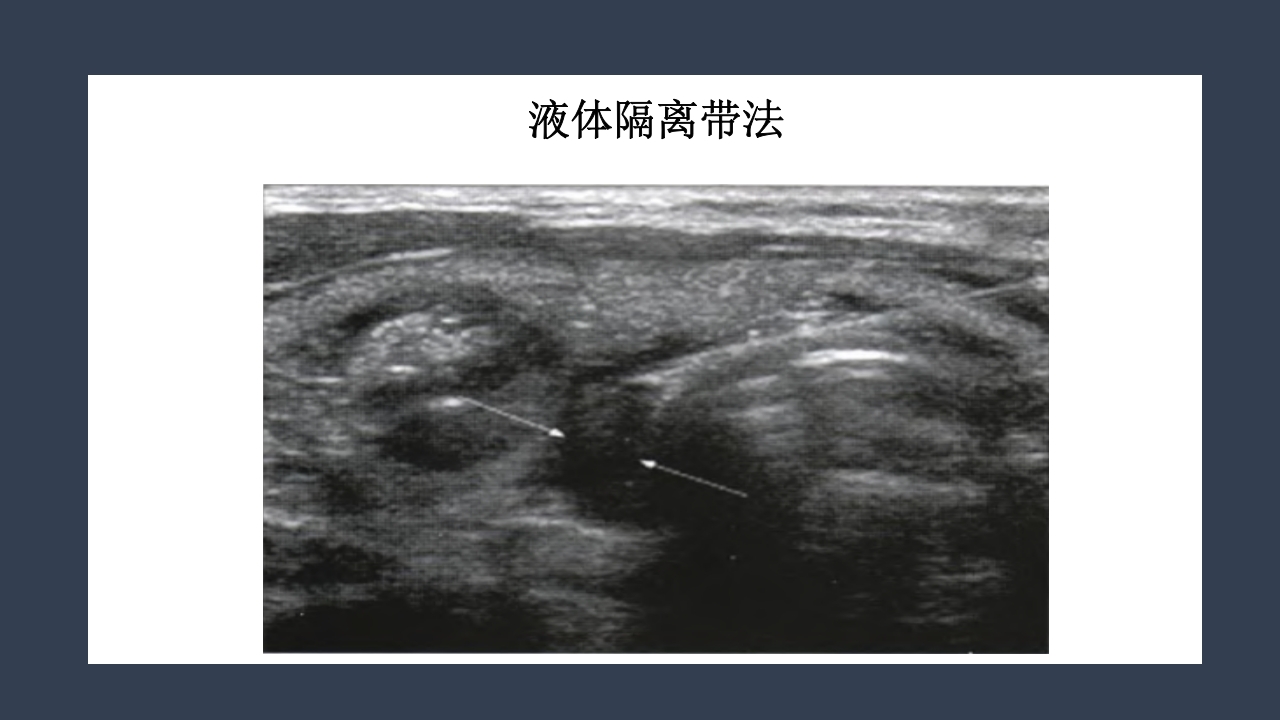

超声引导下甲状 腺结节射频消融 汇报人:xxx 时间:20XX年XX月 研究背景 甲状腺结节的患病率 尸体解剖:50.5% 人群普查可触及:3%-6% 超声发现非触及:20%-60% 男女比可达到1:4 甲状腺良性结节也有恶变可能 研究背景 Benign 甲状腺 结节 Malignant 5%-15% 2%恶性由 良性转变而 来 甲状腺结节的治疗方法 治 疗 传统手术切除 腔镜下切除 微创消融 甲状腺叶 全切除 次全切除 胸骨切迹 锁骨下 胸骨前乳晕 腋窝等 无水 乙醇 硬化 放射性 碘131植入 射频消融 微波消融 激光消融 传统手术切除 6-8CM的手术瘢痕 腔镜下切除 手术时间长,剥离面大,术后 疼痛强,是创伤较大的手术。 射频消融术 RFA治疗甲状腺结节的优势 ①微创或无创治疗技术是医学发展的大趋势。 ②...